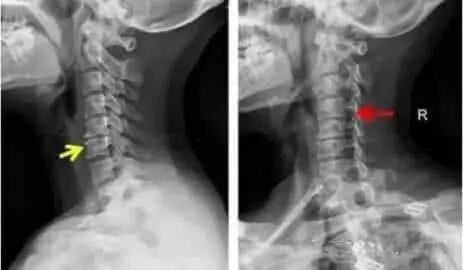

眩晕症状在这里主要是椎动脉型颈椎病的一个主要临床表现。双侧椎动脉供给大脑血流量约占总数的10—15%,供脊髓、脊神经根等组织的血流量约占总数的90%。颈椎屈伸时对椎动脉张力影响不大,一般不引起供血障碍,但在旋转和侧屈时,因为增加了该侧椎动脉张力以致供给大脑的血流量减少,此时,正常人往往可由另一侧椎动脉代偿,以保证大脑、脊椎、脊神经根等的正常血液供应。而在椎动脉型颈椎病患者,早期由于椎节失稳后钩椎关节松动、变位,影响侧方上下横突孔,刺激或压迫椎动脉引起血管痉挛、狭窄、扭曲或曲折等改变;中晚期由于钩椎骨质增生、髓核脱出等直接压迫椎动脉而产生症状。此外,颈椎病多见于中年之后,血管弹性回弹力减弱也是一个不可忽视的原因,如患者同时伴有动脉粥样硬化等就容易加速这一病变过程。